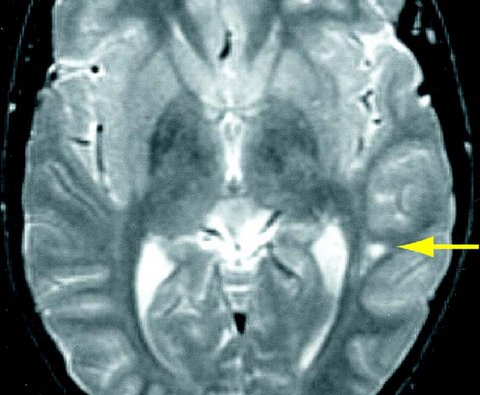

Cerebro de un joven con Síndrome de Asperger

Aunque encontramos el Síndrome de Asperger generalmente encuadrado dentro de los trastornos de espectro autista, posee características diferenciales que le confieren entidad propia. El propio Hans Asperger ya identificó los principales síntomas que diferencian a las personas con este trastorno de las que presentan el perfil típico de los autistas: